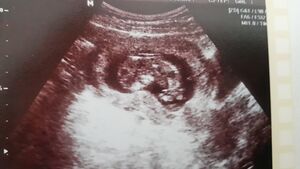

| − | + | [[Datei:Fötus Embryo Ultraschall.jpg|thumb|300px|right|{{ImageCaption|Titel=Dieser Embryo ist rund 14 Millimeter lang.|Urheber=Wingrid Weidinger|Quelle={{ImageMetaSource|Quelle=https://kiwithek.wien/index.php/Datei:SW11.jpg|Linktext=}}|Lizenz={{ImageMetaLicense|URL=https://creativecommons.org/licenses/by-nc-sa/3.0/at/|Lizenz=CC BY-NC-SA 3.0 AT}}}}]] | |

Obwohl der Embryo am Ende des 2. Monats erst rund 14 Millimeter lang ist, zeichnen sich Augen, Nase und Mund schon ab.

Ende des 3. Monats spricht man nicht mehr von einem Embryo sondern von einem Fötus. Er ist schon etwa 8 cm groß.